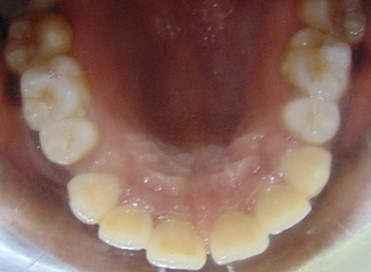

Before

Image 1